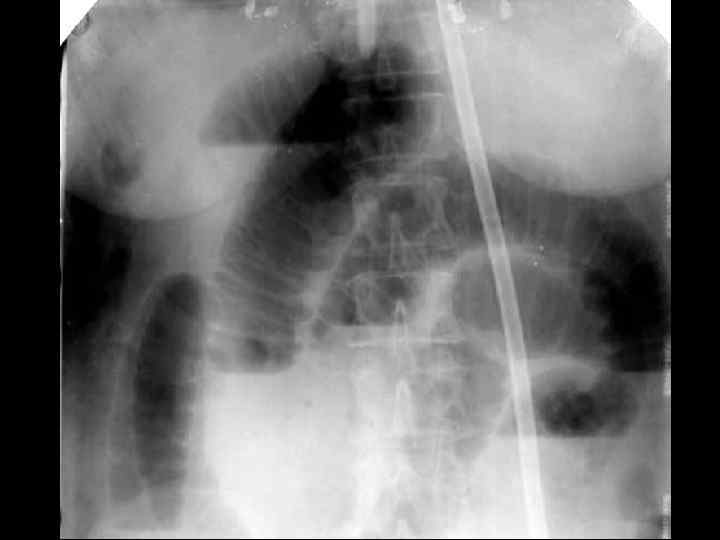

ИРРИГОСКОПИЯ

ОБТУРАЦИОННАЯ ТОЛСТОКИШЕЧНАЯ НЕПРОХОДИМОСТЬ • • опухолевый анамнез возраст больных схваткообразные боли в животе задержка стула и газов "поздняя" рвота вздутие живота интоксикация Симптомы Цеге–Мантейфеля, Обуховской больницы • при рентгенографии- множественные толсто- и тонкокишечные уровни, пневматоз толстой кишки